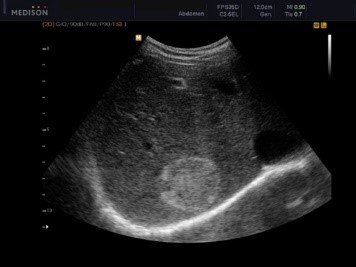

Abses diaqnozunu dəqiqləşdirmək üçün klinik əlmətlərlə yanaşı görüntüləmə və laborator müayinələr aparılmalıdır. Yerli və ümumi sepsis əlamətləri ilə yanaşı USM və ya tomoqrafiyada qaraciyərdə abses boşluğun görünməsi diaqnozu dəqiqləşdirir. Absesdə qaztörədən bakteriyalar olduqda və ya bağırsağa açılarsa içərisində qaz görünür (25%).

Diaqnostik əlamətləri:

• Sistlərdən fərqli olaraq abseslərin sərhədi kəskin olmur, möhtəviyyatının sıxlığı yüksək, hətta nekrotik toxumalar olarsa, heterogen görünür.